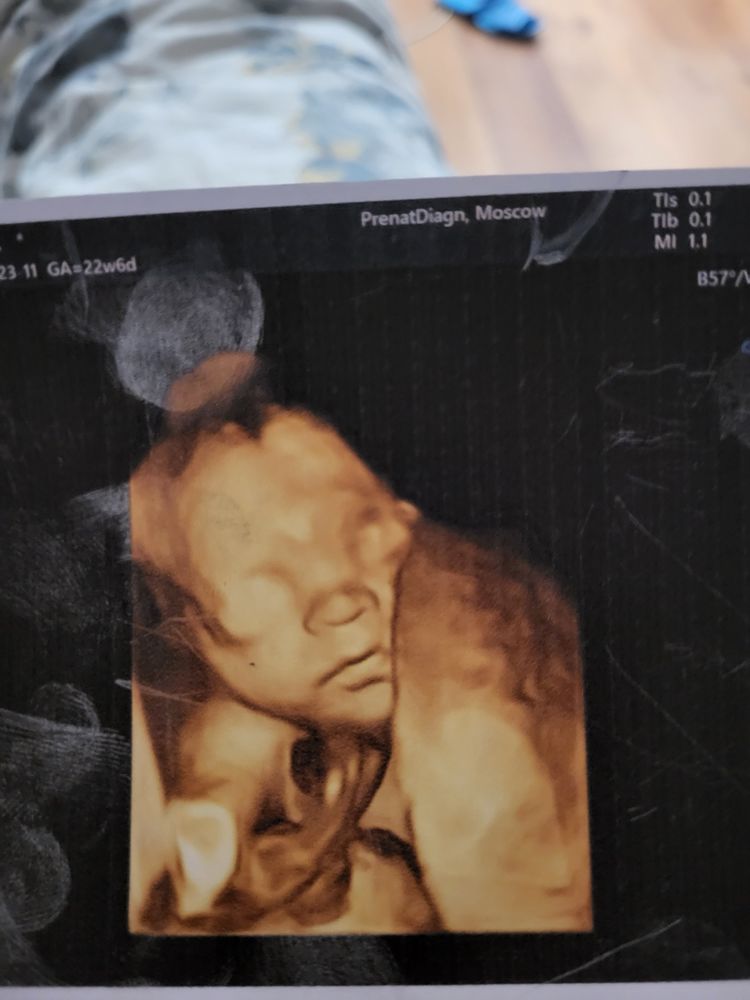

Amelia

Алина, классный снимок, даже кажется, что глазки уже открыты😍. Вот наши снимки, мне показалось, что глазницы как-то низко, а скул не видно, но это наверняка моя дурная голова мне ищет повод понервничать, снимки смазаны наверное просто. Первые 2 сегодняшние, третий неделю назад делали, там вроде обычно выглядят щечки и глазницы

Amelia, да, глазки приоткрыты, на видео видно было, как она их открывает) снимки хорошие! У нас тоже есть не очень удачные, там тоже мне казалось, что с глазницами проблема 🤷🏼♀️ на самом деле, просто ракурс такой и погрешность съемки. У вас замечательная малышка, не переживайте 🤗